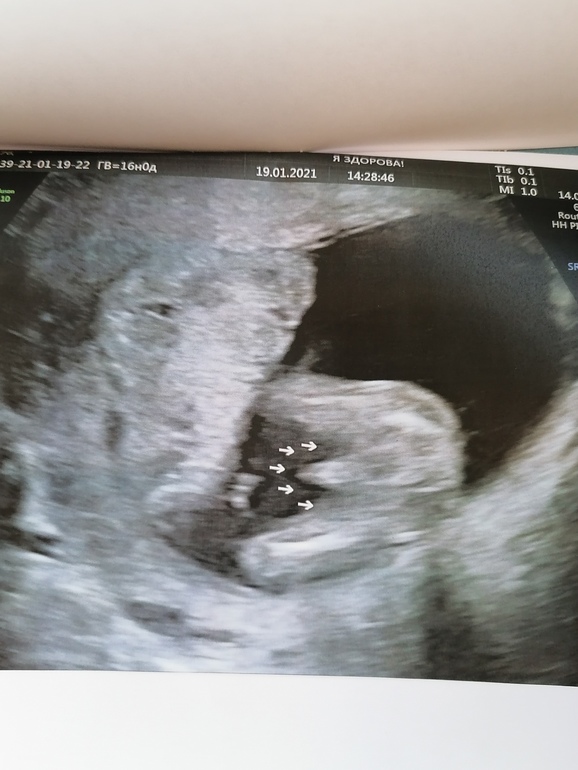

Ну и наш пэрчик💙💙💙🙈 папа аж загордился размеру🙈😂😂😂

Спасибо. Яички сказала врач позже будет видно, пока только перчик

Ну вот в 26 уже вижу бубенцы, а на втором скрининге просто перчик